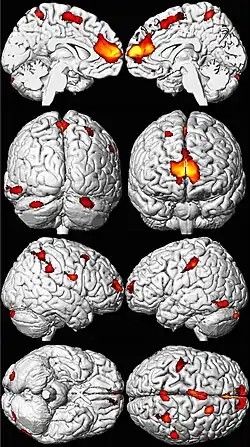

.png)

Lead poisoning can cause a variety of symptoms and signs which vary depending on the individual and the duration of lead exposure.[30][31] Symptoms are nonspecific and may be subtle, and someone with elevated lead levels may have no symptoms.[32] Symptoms usually develop over weeks to months as lead builds up in the body during a chronic exposure, but acute symptoms from brief, intense exposures also occur.[33] Symptoms from exposure to organic lead, which is probably more toxic than inorganic lead due to its lipid solubility, occur rapidly.[34] Poisoning by organic lead compounds has symptoms predominantly in the central nervous system, such as insomnia, delirium, cognitive deficits, tremor, hallucinations, and convulsions.[29]